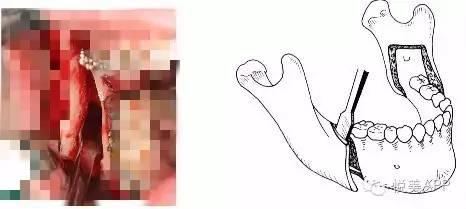

第二步:正颌外科手术,将长出来的部分骨头切除,然后往回推,固定住,形成正确咬合状态~

第一种:下颌骨矫正——将下颌骨截骨,去除一段,整体后退,固定,不但缩短下颌的长度,而且在后退的同时伴有上颌骨向上旋转,下颌角的角度变小,侧面也更好看,如果下巴颏太长,还可以缩短。

悦大咖放一个下颌支矢状骨劈开术,大家不要害怕(看懂示意图就可以了)~

切开与显露

矢状与垂直骨切开

劈开下颌支

从矢状面劈开下颌支

移动远心骨段之后~固定

固定

检查咬合并固定